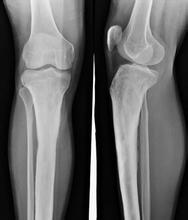

增生性骨关节炎的诊断

根据慢性病史、临床表现和X线所见,诊断比较容易。必要时可做关节滑液检查,以证实诊断。X线改变不能说明是原发性骨关节病,应从病史中明确病损是原发性或继发性。 》》》百看不如一问,咨询专家如何对症治疗